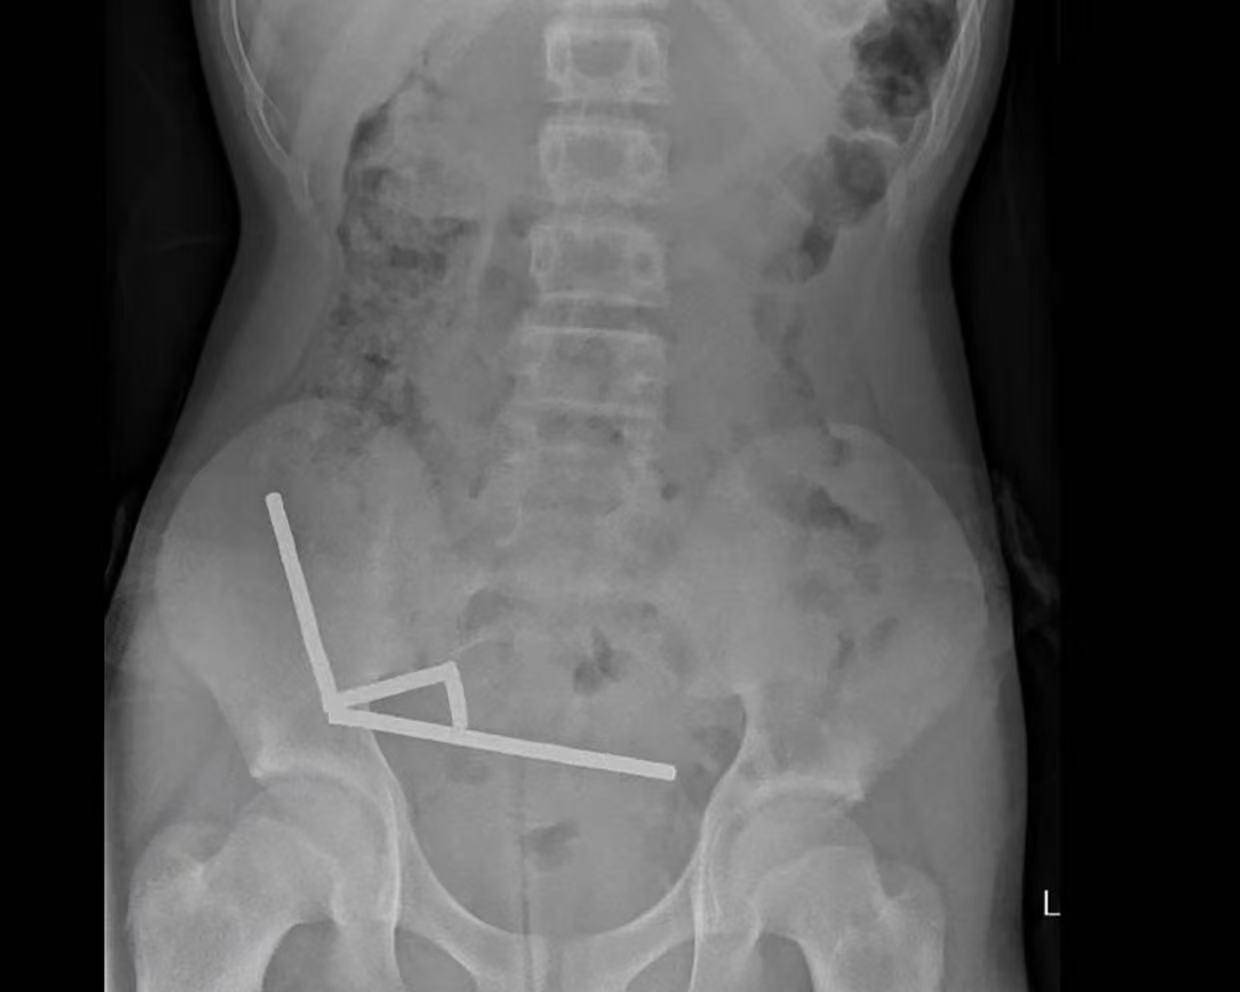

据悉,这名未透露姓名的少年在持续腹痛4天后被送往新西兰北岛的一家医院币优。医生通过X光检查发现,这些磁铁在他的肠道内互相吸附,形成了四条链状结构。

▲X光显示币优,磁铁在男孩体内紧密吸附成链状结构

据该院医生于周五在《新西兰医学杂志》上发表的报告称,外科医生取出了磁铁并切除了部分受损的肠组织币优。磁铁的吸力导致男孩小肠及盲肠(属大肠的一部分)出现四处组织坏死。该男孩在住院8天后康复出院。

医生介绍,男孩大约一周前吞下了80至100颗大功率钕磁铁,每颗尺寸为5×2毫米币优。报告称,这些磁铁通过一家跨境电商平台购买。